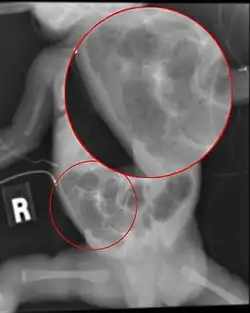

![]() تصوير شعاعي of a baby with necrotizing enterocolitis تصوير شعاعي of a baby with necrotizing enterocolitis | |